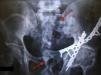

Se encontró una respuesta favorable al tratamiento en 7 de los pacientes (87,5%). Se presentó un caso que solo tuvo un aumento en su escala del IIFE de 2 puntos. En este paciente identificamos edad de 56años, presencia de hipertensión y tabaquismo. Además, se evidenció una fractura inestable de pelvis con luxación de hueso coxal, como se muestra en la figura 1. Ningún otro participante presentó trauma con inestabilidad de anillo pelviano.

DiscusiónEl manejo de la lesión uretral en la fractura de pelvis sigue siendo controvertido, debido a que no se han mostrado resultados concluyentes de qué tratamiento desencadena menor incidencia de DE e incontinencia urinaria17. En nuestro estudio todos los pacientes se sometieron a realineación uretral de urgencia, presentándose DE en el 100% de ellos, y en ninguno incontinencia urinaria. Posteriormente se llevó a cabo una uretroplastía témino-terminal como tratamiento definitivo (fig. 2).

a)Radiografía simple de pelvis. Se muestra fractura de rama isquiopúbica (flechas) previo a uretroplastia. b)Cistouretrograma de choque previo a uretroplastia. Presenta estenosis de uretra bulbar (punta de flecha); sonda de cistostomía (asterisco). c)Radiografía simple de pelvis del mismo paciente, 10semanas tras el trauma. d)Cistouretrograma retrógrado normal posterior a uretroplastia.